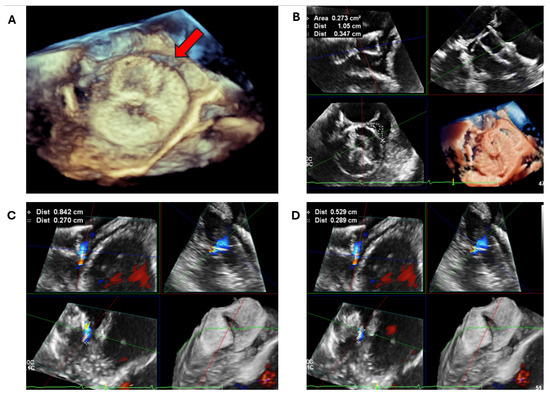

2.2.1. LAA Thrombus Assessment

3.2. Peri-Device Leaks